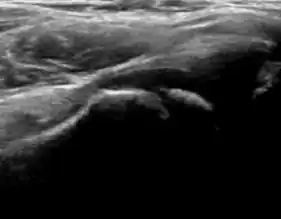

During childhood, ultrasound is a quick method to assess hip pain and quite often may be used to avoid use of irradiating techniques, such as radiography or CT. Ultrasound allows evaluation of joint effusion, synovial thickening and neovascularity, the bone/cartilage contour, and the femoral head-neck alignment. Although sonography is extremely sensitive in detecting increased synovial fluid, it is nonspecific and cannot be used with accuracy to determine the type of fluid. Transient synovitis of the hip, despite being the most frequent cause of pain in children between 3 and 10 years, remains a diagnosis of exclusion. It usually shows anechoic fluid, but echogenic fluid can also be found. The effusion is considered pathologic when it is measured at >2 mm in thickness. The differential diagnosis is wide, including osteomyelitis, septic arthritis, primary or metastatic lesions, LCPD, and SCFE. Discrimination from septic arthritis is challenging, often requiring joint aspiration. In septic arthritis, US is able to demonstrate a hip joint effusion, synovial thickening, and cartilage damage, although the appearances are nonspecific.[1]

A step between the head and the physis can be detected in children with SCFE, while abnormalities in the femoral head contour may suggest the presence of LCPD. In both cases, radiographs are mandatory to confirm diagnosis and severity (Figure 12).[1]

Figure 12:

Normal ultrasound appearance of the femoral head-neck junction. -

Joint effusion in transient synovitis of the hip. -

Flattening of the femoral head in a patient with Perthes disease. -

Step in the femoral head-neck junction in a patient with SCFE.